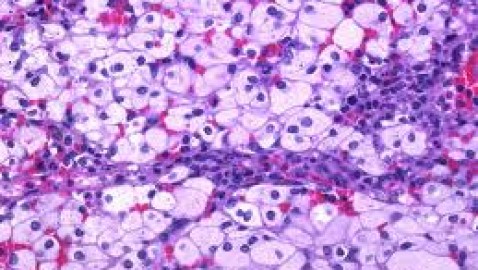

Alteraciones congénitas del catabolismo de lípidos complejos

Existe un grupo de enfermedades hereditarias caracterizadas por trastornos metabólicos resultantes en acumulación de lípidos complejos en diversos tejidos. En general, se manifiestan desde la niñez y afectan...